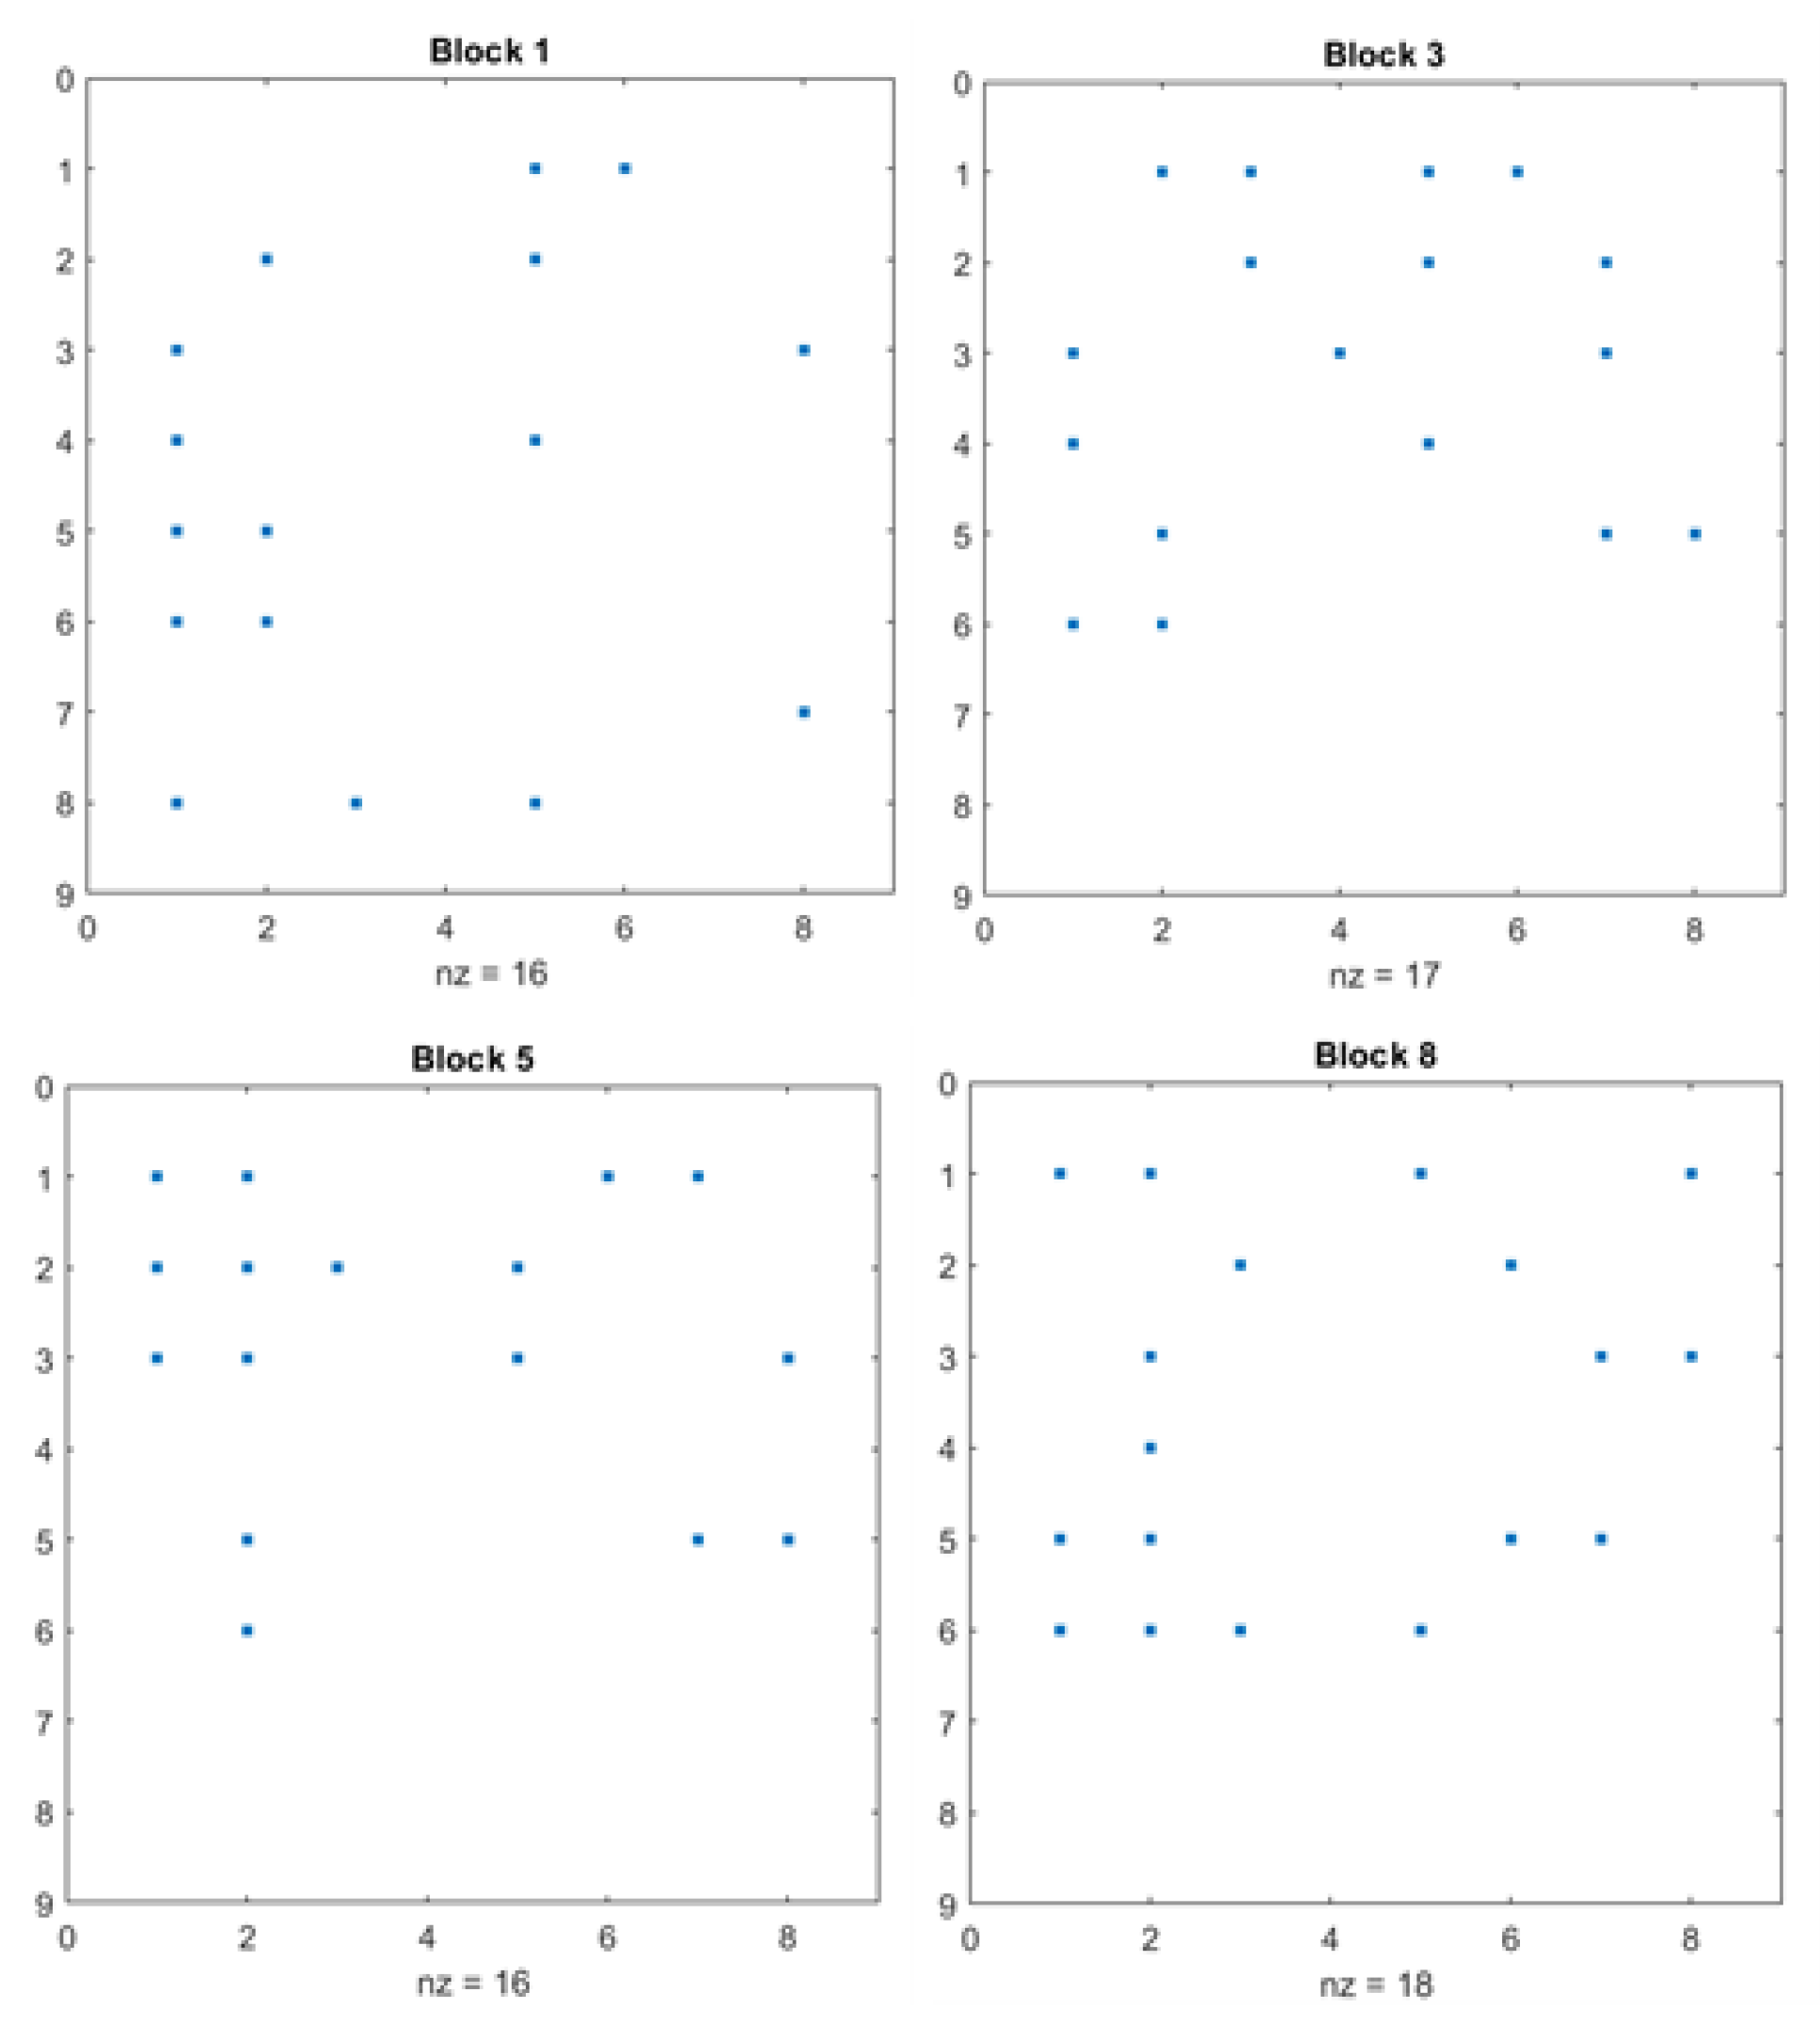

4.5. Sparsity Balance Analysis